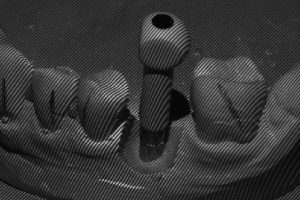

- Ryc. 14_Przykręcenie skan lokatora do repliki implantu Ankylos C/X w modelu roboczym.

- Ryc. 15_Model ze skan lokatorem, widok ze skanera.

- Ryc. 16_Skan komputerowy, widok modelu i skan lokatora.

- Ryc. 17_Skan komputerowy, widok modelu z kęskiem zwarciowym.

Po zamontowaniu tzw. skan lokatorów i zeskanowaniu modelu, wypełniany jest formularz zamówienia na łącznik. Zawiera on wszystkie niezbędne informacje dotyczące sposobu wykonania łącznika zgodnie z życzeniem zamawiającego takie, jak: rodzaj materiału, kompresja tkanek miękkich, profil wyłaniania, angulacja, wysokość okluzyjna, głębokość posadowienia poddziąsłowo stopnia dla korony itp. Następnie formularz ten (tzw. Atlantis WebOrder) łącznie ze skanami przesyłany jest do Centrum Projektowania i Frezowania Atlantis. W odpowiedzi na zamówienie otrzymujemy wirtualny projekt łącznika do akceptacji w programie Atlantis VAD. W zależności od tego, czy projekt spełnia nasze oczekiwania, czy też wymaga zmian, do Centrum Projektowania wysyłana jest określona informacja. Po ostatecznym za- akceptowaniu projektu łącznika, zamówienie otrzymuje status realizacji i łącznik przekazy- wany jest do produkcji. Po kilku dniach łącznik trafia do laboratorium, gdzie jest sprawdzany na modelach gipsowych i odsyłany do kontroli klinicznej.